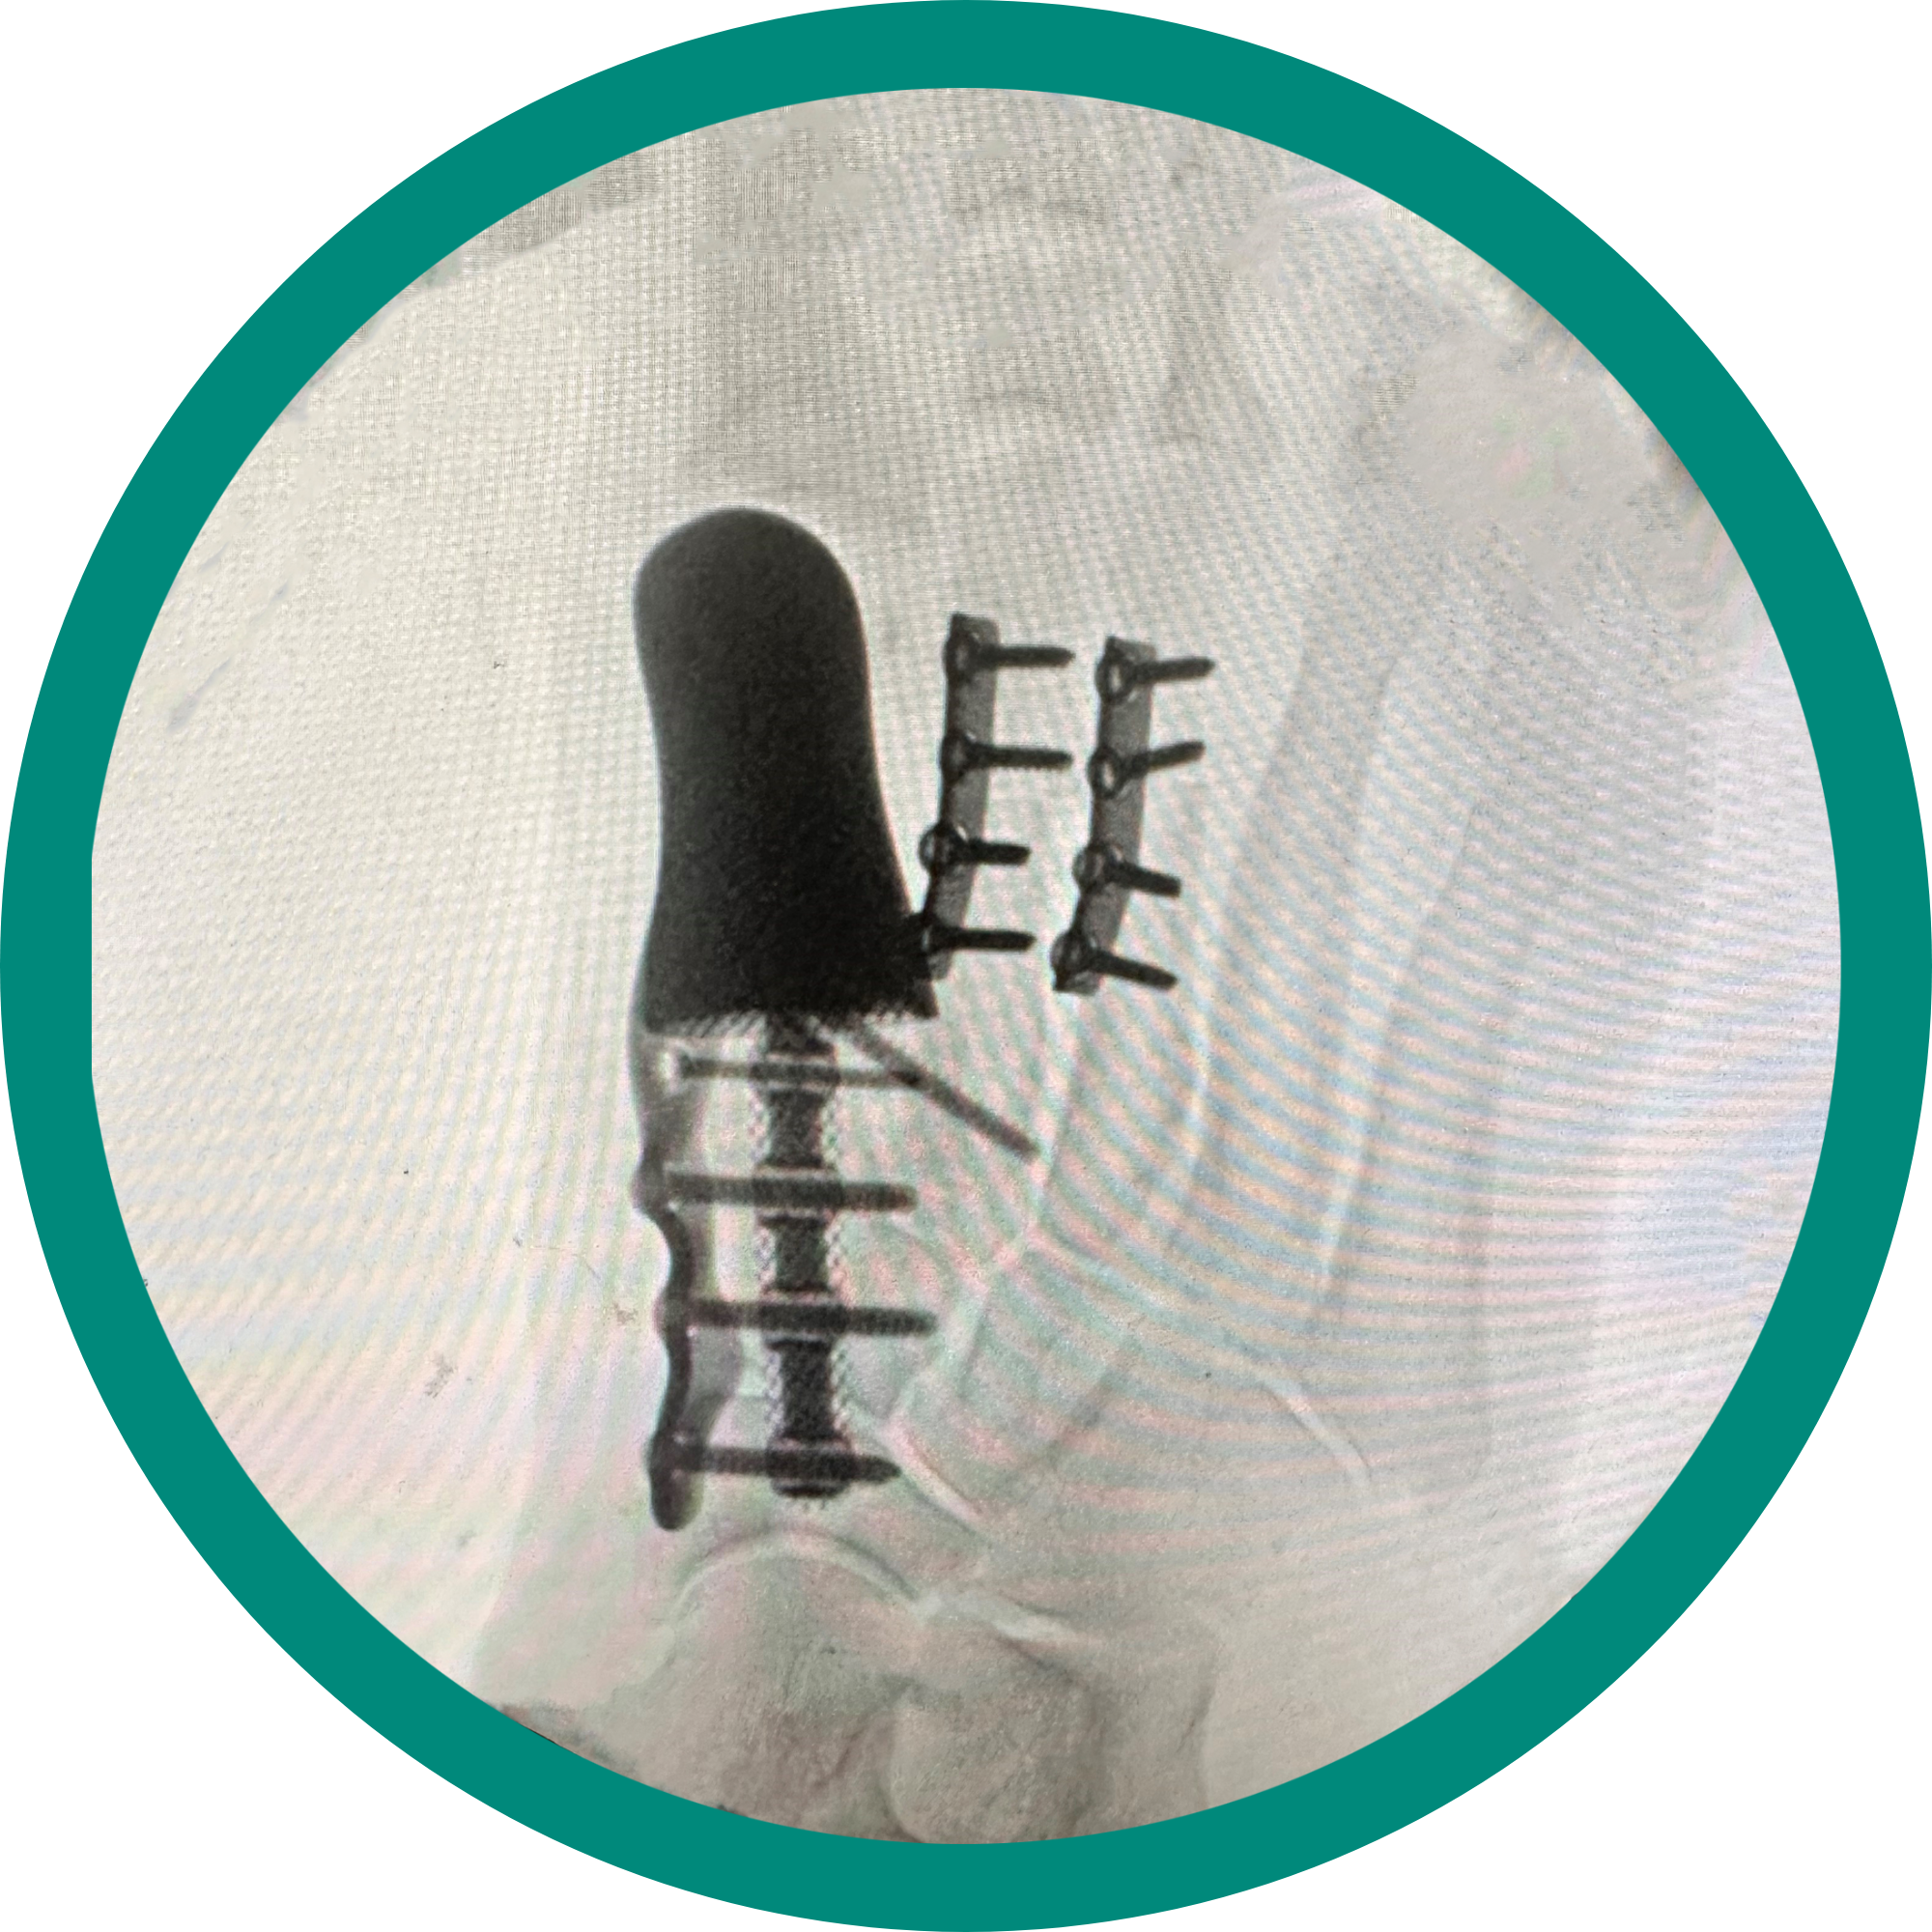

Complex trauma

Dr. Stevens’ practice is one of the few foot and ankle specialists in Illinois. He provides various care options including, but not limited to, revision surgeries, reconstruction fusions and complex trauma repairs. He also ranks in the Top 1% in patient experience nationally.

Complex reconstruction

Fractures